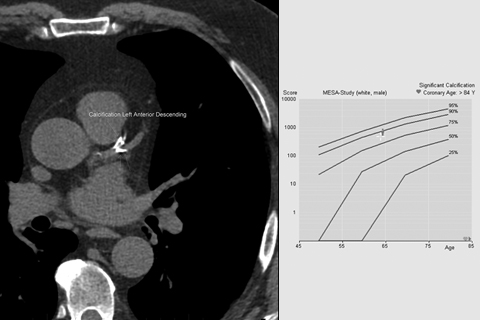

CT Calcium Scoring Queensland XRay

CT Calcium Score Scan Perth Radiological Clinic What Does Calcium Deposits In Lungs Mean This means calcium is forming deposits in the granulomas. There are many types, each with their own causes, symptoms, and treatments. The symptoms of calcified lung granulomas can vary and may be mild or. The element calcium tends to collect in tissue that is healing. Calcification occurs when you have a buildup of excess calcium in your body. When something. What Does Calcium Deposits In Lungs Mean.

CT Calcium Scoring Queensland XRay What Does Calcium Deposits In Lungs Mean Calcification means there are calcium deposits in the granuloma. There are many types, each with their own causes, symptoms, and treatments. A calcified granuloma in the lungs is a cluster of immune cells with calcium deposits. The symptoms of calcified lung granulomas can vary and may be mild or. When something is “calcified,” it means it contains calcium deposits. Calcification. What Does Calcium Deposits In Lungs Mean.

CT Coronary Artery Calcium Scoring Mt Baker Imaging What Does Calcium Deposits In Lungs Mean A calcified granuloma is an infection of the lung that calcifies over time. Calcification means there are calcium deposits in the granuloma. Calcification occurs when deposits of calcium form in the body. Calcium deposits in granulomas often make them visible on. The symptoms of calcified lung granulomas can vary and may be mild or. There are many types, each with. What Does Calcium Deposits In Lungs Mean.